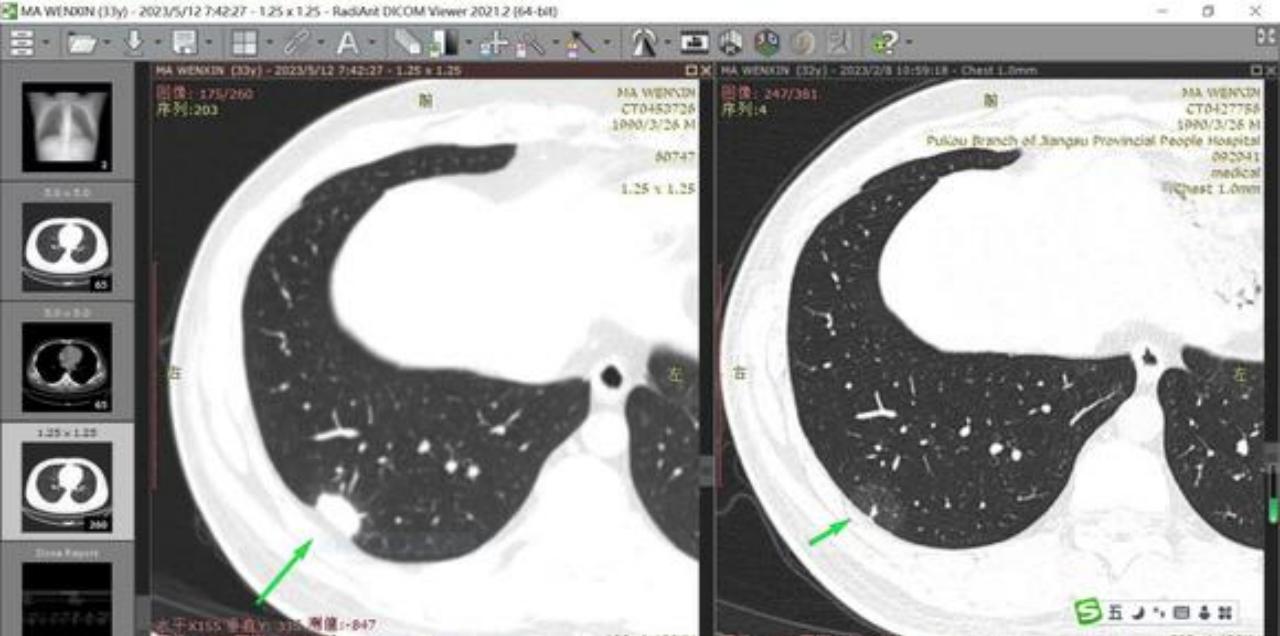

2022年5月,通过单位组织的体检,发现了左肺下叶后基底段一枚5x5的纯磨玻璃结节。2022年12月底,我感染了新冠。2023年2月复查CT,左肺下叶的5mm的纯磨玻璃没有变化,但右肺下叶外基底段多了一个3mm的实性结节、和一个右下肺胸膜下27mm的斑片状模糊影,当时医生考虑27mm的模糊影是炎性的,让继续观察三个月(期间找了省中医的主任医师开了三个月的夏枯草类中药,没有服用消炎类西药)。

但5月复查,医生告知27mm的模糊影变成了23mm的实性结节,说是进展太快,不排除恶性肿瘤,让我尽快转诊专家,做下一步治疗打算。现在的我万分焦急,感觉天都塌了,作为家里的顶梁柱,上有老、下有小。

这是2023年5月的